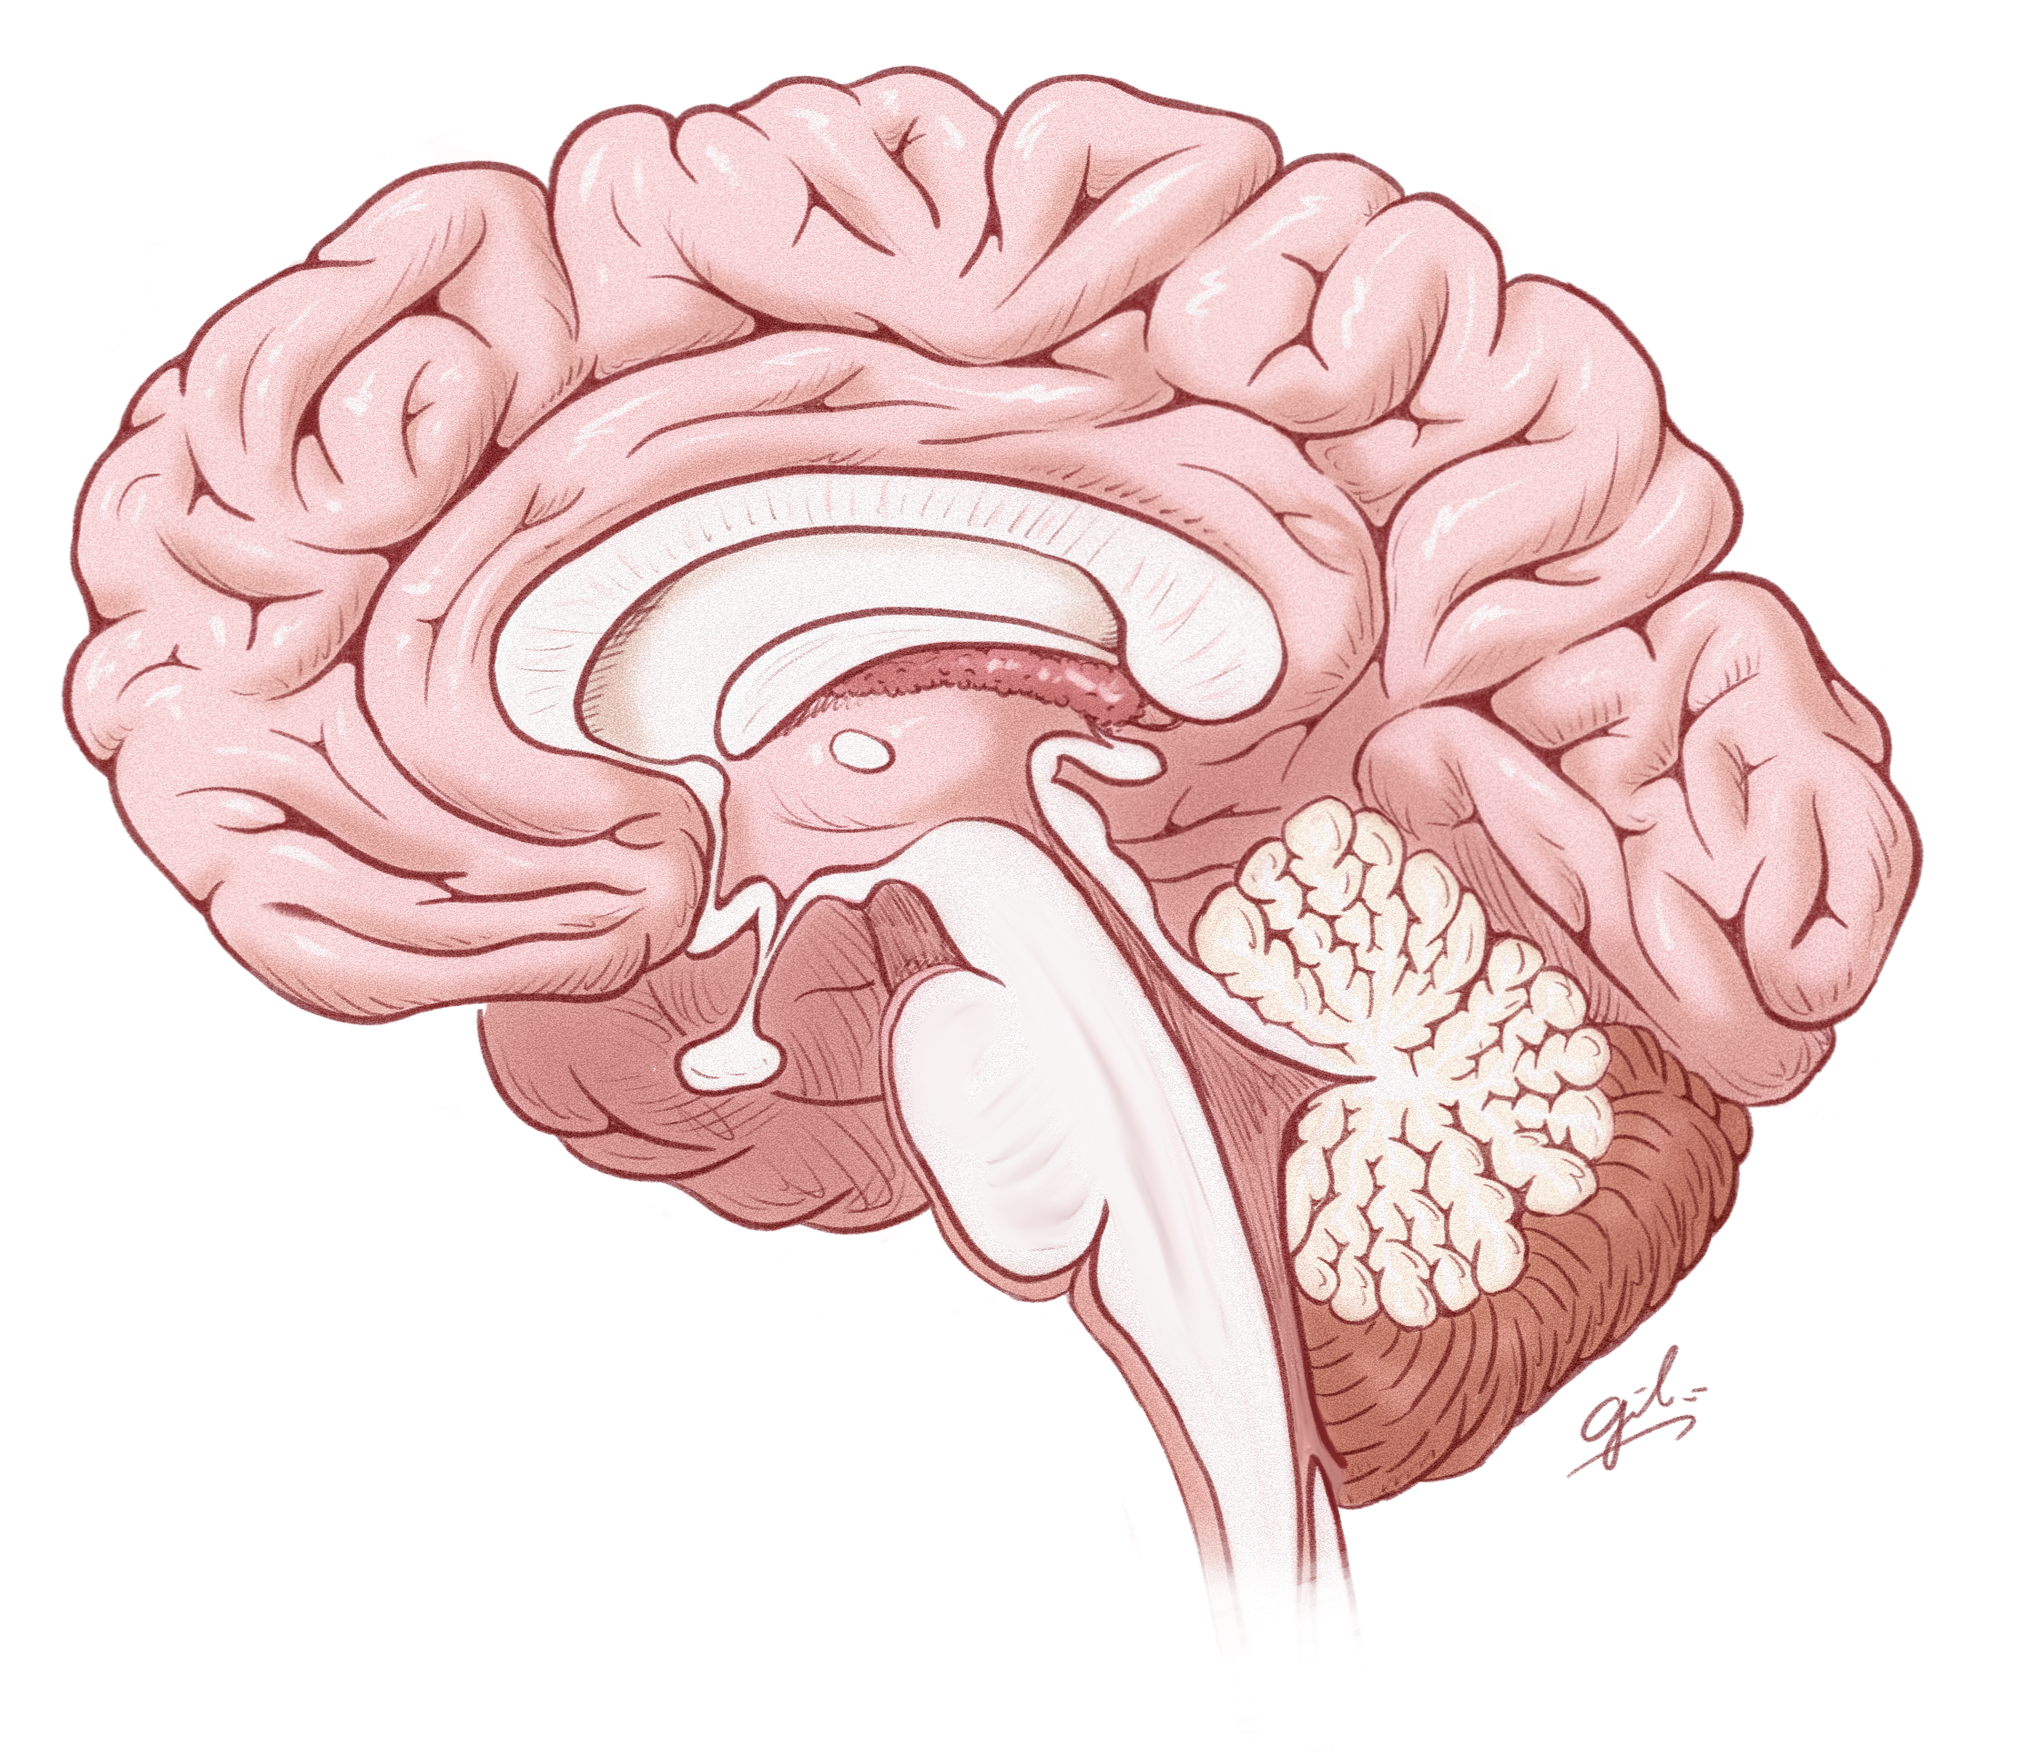

The BRAIN Lab brings together seven labs to uncover how brain cells die and survive, driving discoveries in Parkinson’s, Alzheimer’s, and stroke. We pioneered Parthanatos and identified key disease genes, with therapies now advancing toward the clinic.

UNRAVELING THE MYSTERIES OF NEURODEGENERATION